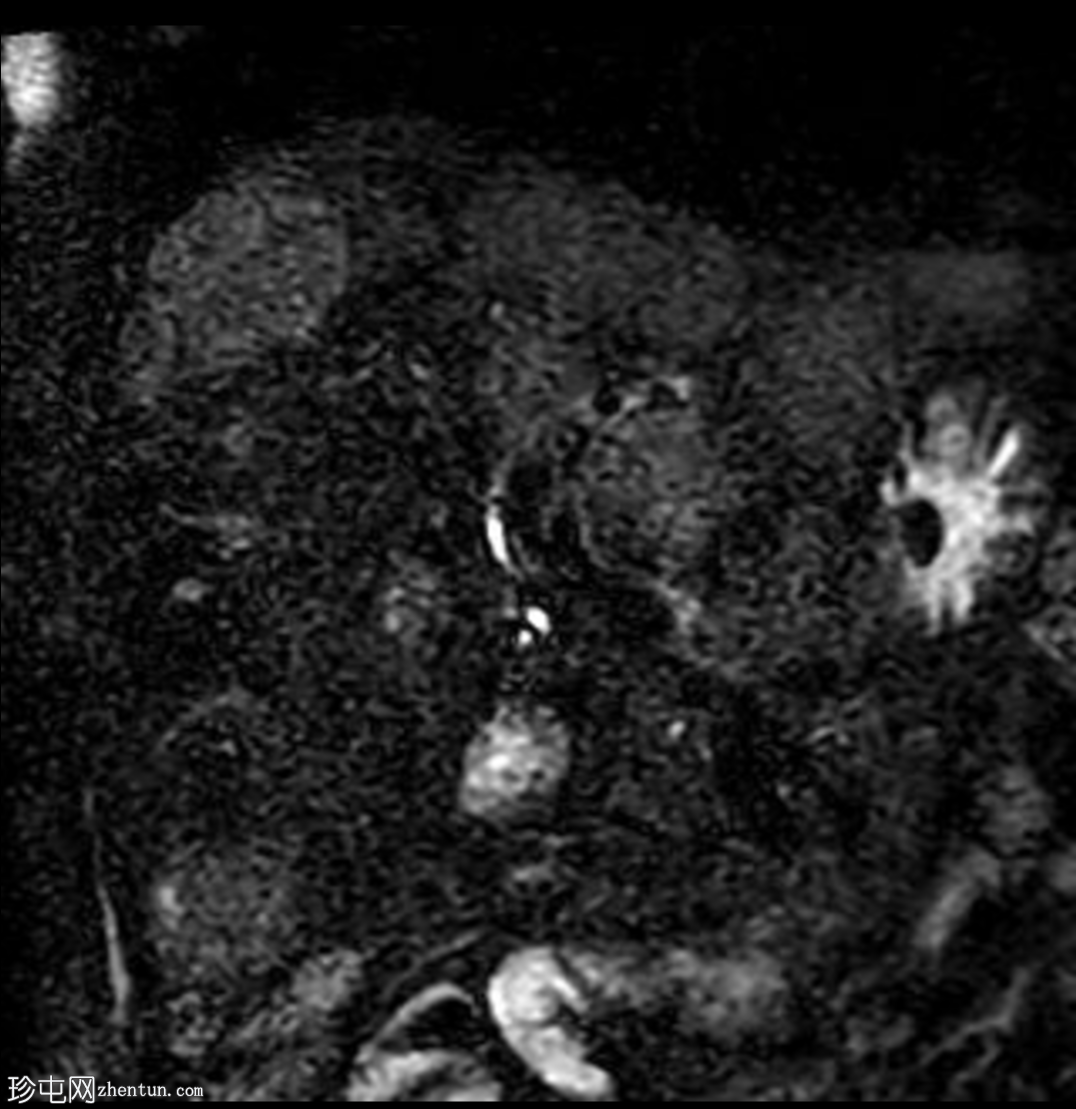

MRI

轴位

T2加权像

肝脏多发病灶,其中数个病灶呈中心T2高信号。

磁共振胰胆管造影(MRCP)显示肝转移灶处存在多处短段胆管狭窄和闭塞,上游胆管扩张,提示

肿瘤

直接压迫/浸润。

肝总管(CHD)和胆总管(CBD)通畅,管径正常。

无胆总管结石。

肝转移灶中心T2高信号最可能是由于肿瘤快速生长导致的中心坏死。